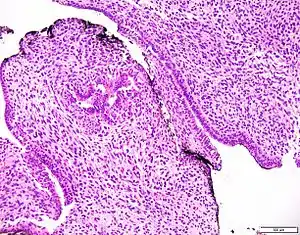

Prostatic stromal tumour of uncertain malignant potential (PSTUMP) is a rare tumour of the prostate gland stroma that may behave benign or like cancer.

| Prostatic stromal tumour of uncertain malignant potential. H&E stain. | |